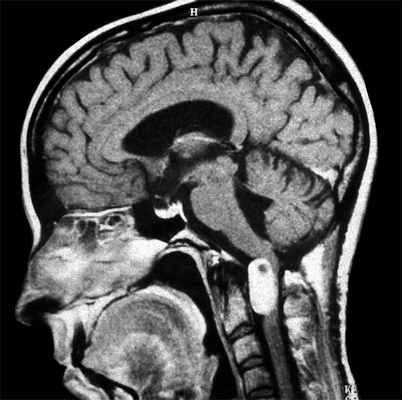

МРТ при нейрофиброматозе - что покажет

МРТ головного мозга при нейрофиброматозе чаще всего осуществляют для дифференциальной диагностики заболевания. Нейрофиброматоз - это наследственное заболевание с характерными изменениями на коже (нейрофибромами), изменениями в нервной системе и возможным поражением других органов. Первичный нейрофиброматоз потребует проведения МРТ головного мозга и спинного мозга, желательно на томографе с индукцией магнитного поля не менее 1.5 Тесла, и последующей консультации и консилиума врачей, включающего дерматолога, отоларинголога, окулиста, невролога и генетика.

Многие пациенты с диагнозом нейрофиброматоза страдают мигренью. У некоторых людей развиваются опухоли головного мозга, хотя это бывает редко и чаще всего не вызывает заметных неврологических нарушений. Однако опухоли в определенных частях мозга иногда провоцируют:

- изменения личности;

- слабость на одной стороне тела;

- трудности с балансом и координацией.